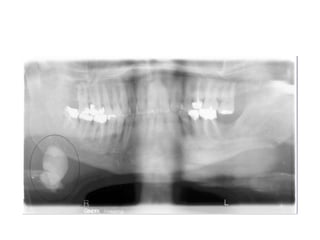

• Salivary calculi cause obstruction within the duct lumen

• Calculi may form in ducts within the gland or in the

• submandibular gland is most frequently involved,

• The parotid gland is the next most commonly involved,

• Calculi are usually unilateral, although multiple stones in

• The typical signs and symptoms of calculi associated

• The calculi may be detected by palpation and on

• Radiography is helpful in confirming the diagnosis and